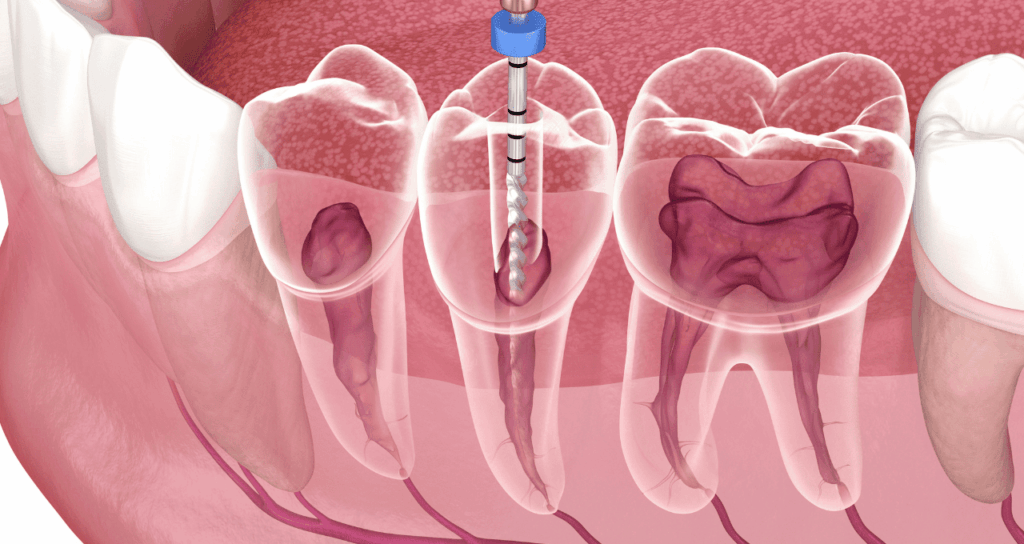

虫歯が重度に進行して神経まで達してしまった場合や、過去に治療した歯の根の先に膿が溜まってしまった場合に、汚染された神経や細菌を取り除き、根の中を洗浄・消毒して、再び細菌が入らないように密閉します。

なぜ、これほどまでに根管治療は難しく再発しやすいのでしょうか。その理由は歯の根の中の構造にあります。根管の直径はわずか1mm以下と非常に細く、しかも真っ直ぐではありません。

湾曲していたり、途中で枝分かれしていたり、網の目のように複雑に入り組んでいたりと、人によって千差万別です。さらに、根の中は暗くて狭いため、肉眼でその全貌を捉えることは物理的に不可能です。

根の中がきれいになったら、最終的に空洞を封鎖する「根管充填(こんかんじゅうてん)」を行います。

ここで隙間ができてしまうと、再び細菌が繁殖するスペースを与えてしまいます。

当院では、ガッタパーチャと呼ばれるゴム状の材料やバイオセラミック系の材料を使用し、根の先端から入り口まで隙間なく緊密に充填します。

熱を加えて溶かし込んだり圧力をかけたりすることで、複雑な枝分かれ部分にも材料を行き渡らせ、細菌の侵入経路を完全に遮断します。